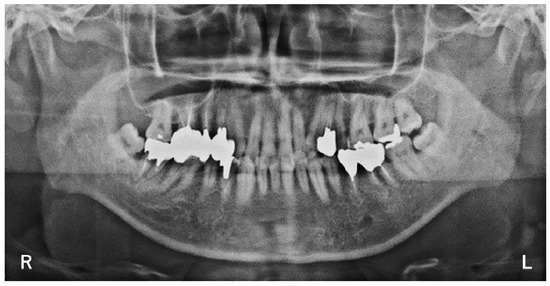

2. Case

3. Examination